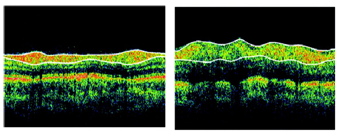

Optical Coherence Tomography (OCT) is a promising as well as noninvasive retina imaging technique that provides cross-sectional images of the eye retina with quality resolution pictures. During the OCT process, six linear scans centered on the Optical Nerve Head (ONH) is obtained, and the OCT software derives the ONH parameters in an automatic manner. The scan also gives horizontal and vertical cup-to-disc ratios. For the measurement of Retinal Nerve Fibre Layer (RNFL), the usable RNFL thickness circle scan mode which consists of 3 scans that are circular with twice the radius of 3.4mm centered on the ONH should be used. Thus the overall, average and quadrant RNFL thicknesses should be calculated automatically. At the OCT scanning, the subject the clinicians should give instructions to fixed on a target internally to bring the ONH within view of the practioner. For the analysis of RNFL thickness the best-quality scan such as focused picture of the fundus, sufficient signal-to-noise ratio, and the presence of a centered, circular ring around the ONH should be chosen. The average of the RNFL thicknesses in each quadrant of the study eye should be compared with the AD patients and the normal subjects. The OCT image of normal and AD is shown on Figure 3. From the figure itself we can identify the loss of nerve layers as well as the thinning of the layers.

Figure 3 OCT image of Normal (left) and AD (right) (Source, SGM&RF)